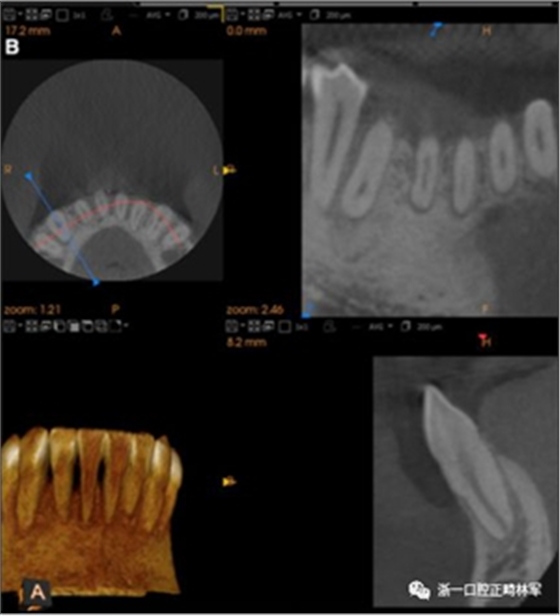

之前和之后的三維圖像(圖19)突出顯示在下頜右側(cè)尖牙面?zhèn)缺砻嫔瞎堑脑黾右约扒把姥栏恢玫母纳啤S捎谙骂M切牙的伸長(zhǎng)被認(rèn)為是不嚴(yán)謹(jǐn)?shù)?,因此輕度前牙開(kāi)合沒(méi)有被矯正。

圖19.A,治療前和B,治療后的三維圖像。注意牙根位置的改善和(右下圖像)右側(cè)尖牙面?zhèn)裙琴|(zhì)的形成。